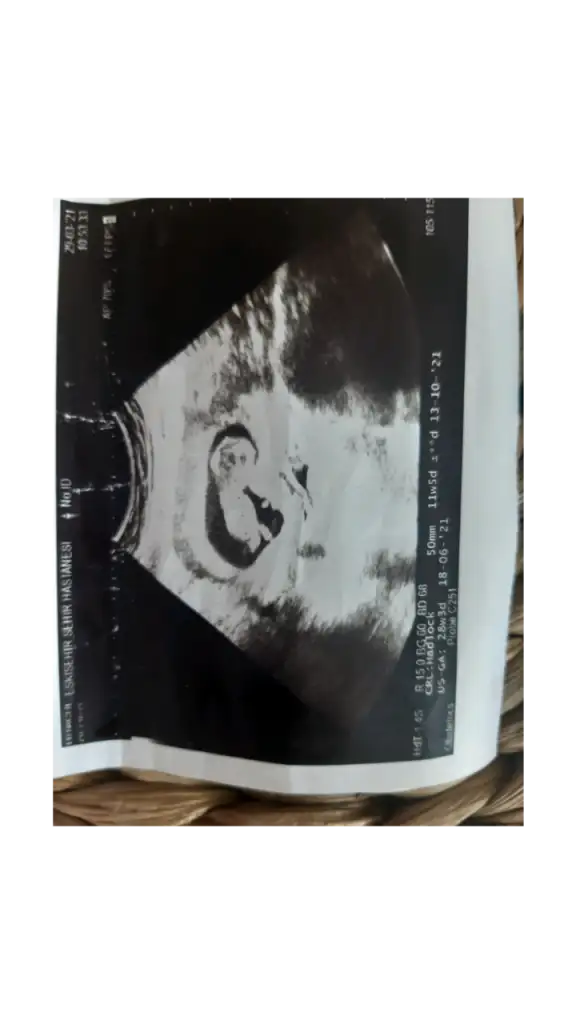

benimkini de yorumlar misiniz 11 haftalikErkek sanki

Erkek gibi sanki olursa 12-13 hafta paylaşın sizinmi kızınız vardı dimi11 haftalik benimkini de yorumlar misiniz

Bizede bakarmısın 12 haftalık bebeğimKız görünüyor

Nubu göremedim varsa USG paylaşın sanki kız tipi varBizede bakarmısın 12 haftalık bebeğim